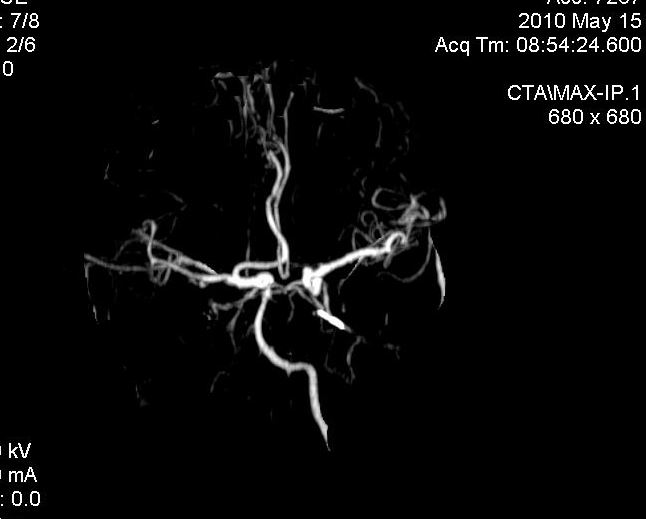

男.60岁,渐进性意识不清,ct检查双侧额颞顶部硬膜下血肿,开颅术后行脑血管cta,大脑中动脉起始部见一瘤状血管扩张。请各位老师留下宝贵意见

太常见了,报动脉瘤就可以

符合动脉瘤表现。

符合动脉瘤表现。

动脉瘤。

颅内动脉瘤。

后重建做得不是很好看,要将维蒂斯环充分显示,最好在增加一个mip。这样不好定位。

小动脉瘤

典型

符合动脉瘤的表现

动脉瘤

符合动脉瘤表现。

小动脉瘤

典型